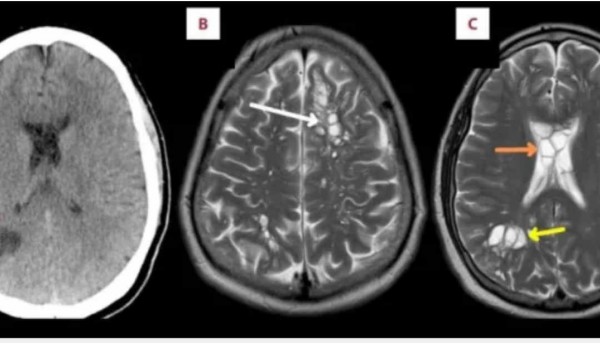

Un paciente de 52 años en la Florida, Estados Unidos, fue al médico por migrañas crónicas que cada vez eran más frecuentes y los medicamentos que usaba ya …